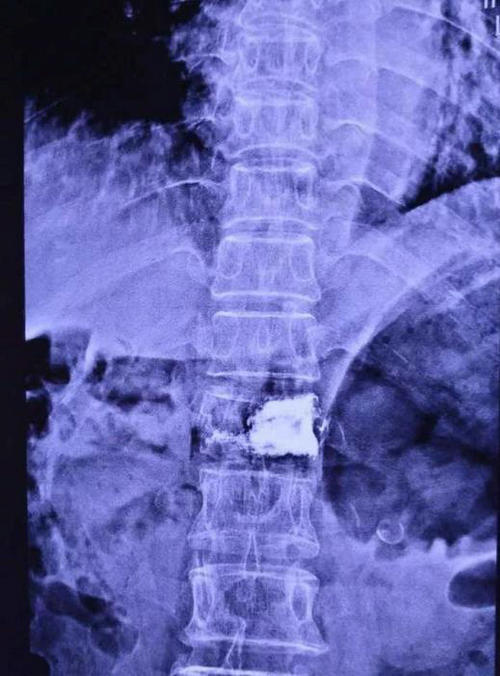

张长江主任指示付卫平,余耀坤两位医师迅速完善相关检查,明确诊断,排除手术禁忌症。各项检查结果都证实了张长江主任的判断——胸12椎体压缩骨折。

▲ 患者术前正侧位影像